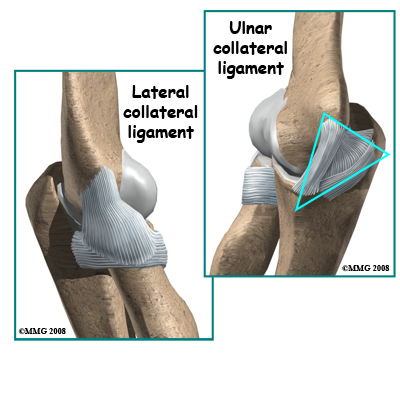

In the elbow, two of the most important ligaments are the ulnar collateral ligament (UCL) and the lateral collateral ligament. The UCL is also known as the medial collateral ligament. The ulnar collateral ligament is on the medial (the side of the elbow that's next to the body) side of the elbow and the lateral collateral is on the outside. The ulnar collateral ligament is a thick band of ligamentous tissue that forms a triangular shape along the medial elbow. It has an anterior bundle, posterior bundle, and a thinner, transverse ligament.

Together these two ligaments, the ulnar (or medial) collateral and the lateral collateral, connect the humerus to the ulna and keep it tightly in place as it slides through the groove at the end of the humerus. These ligaments are the main source of stability for the elbow. They can be torn when there is an injury or dislocation of the elbow. If they do not heal correctly the elbow can be too loose or unstable. The ulnar collateral ligament can also be damaged by overuse and repetitive stress, such as the throwing motion.